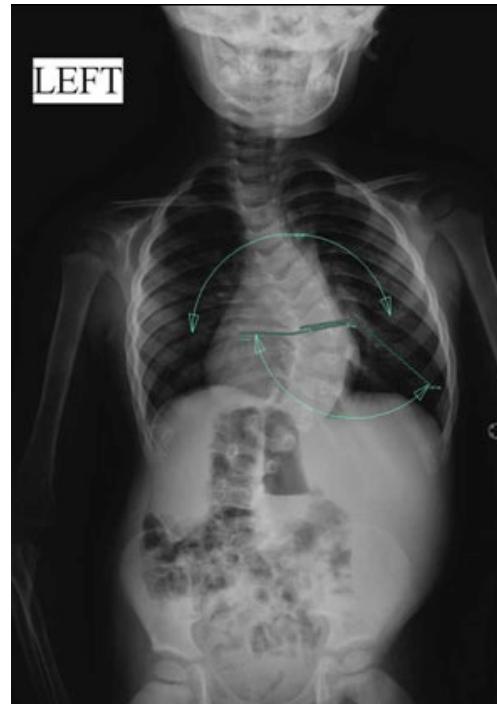

Adolescent Idiopathic Scoliosis

- Definition: Coronal plane spinal deformity most commonly presenting in adolescent girls from ages 10 to 18

Imaging:

Severity Grades:

- Mild: 10-25°

- Moderate: 25-45°

- Severe: >45°

Treatment Based on Severity:

- Observation: Mild curves, depending on age and skeletal maturity

- Bracing: Moderate curves (25-45°) in growing patients

- Surgery: Severe curves (>45°) or progressive curves